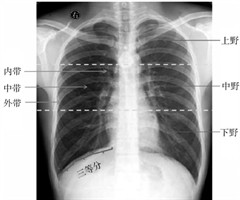

径向探头超声支气管镜联合导引鞘下肺活检在肺外周结节中的应用

【摘要】目的:评估径向探头超声支气管镜联合导引鞘(RP-EBUS-GS)下肺活检对肺外周结节的诊断效果。方法:回顾性分析2021年7月—2023年5月于南昌医学院第一附属医院使用RP-EBUS-GS配套的细胞刷(RP-EBUS-GS刷检)和...